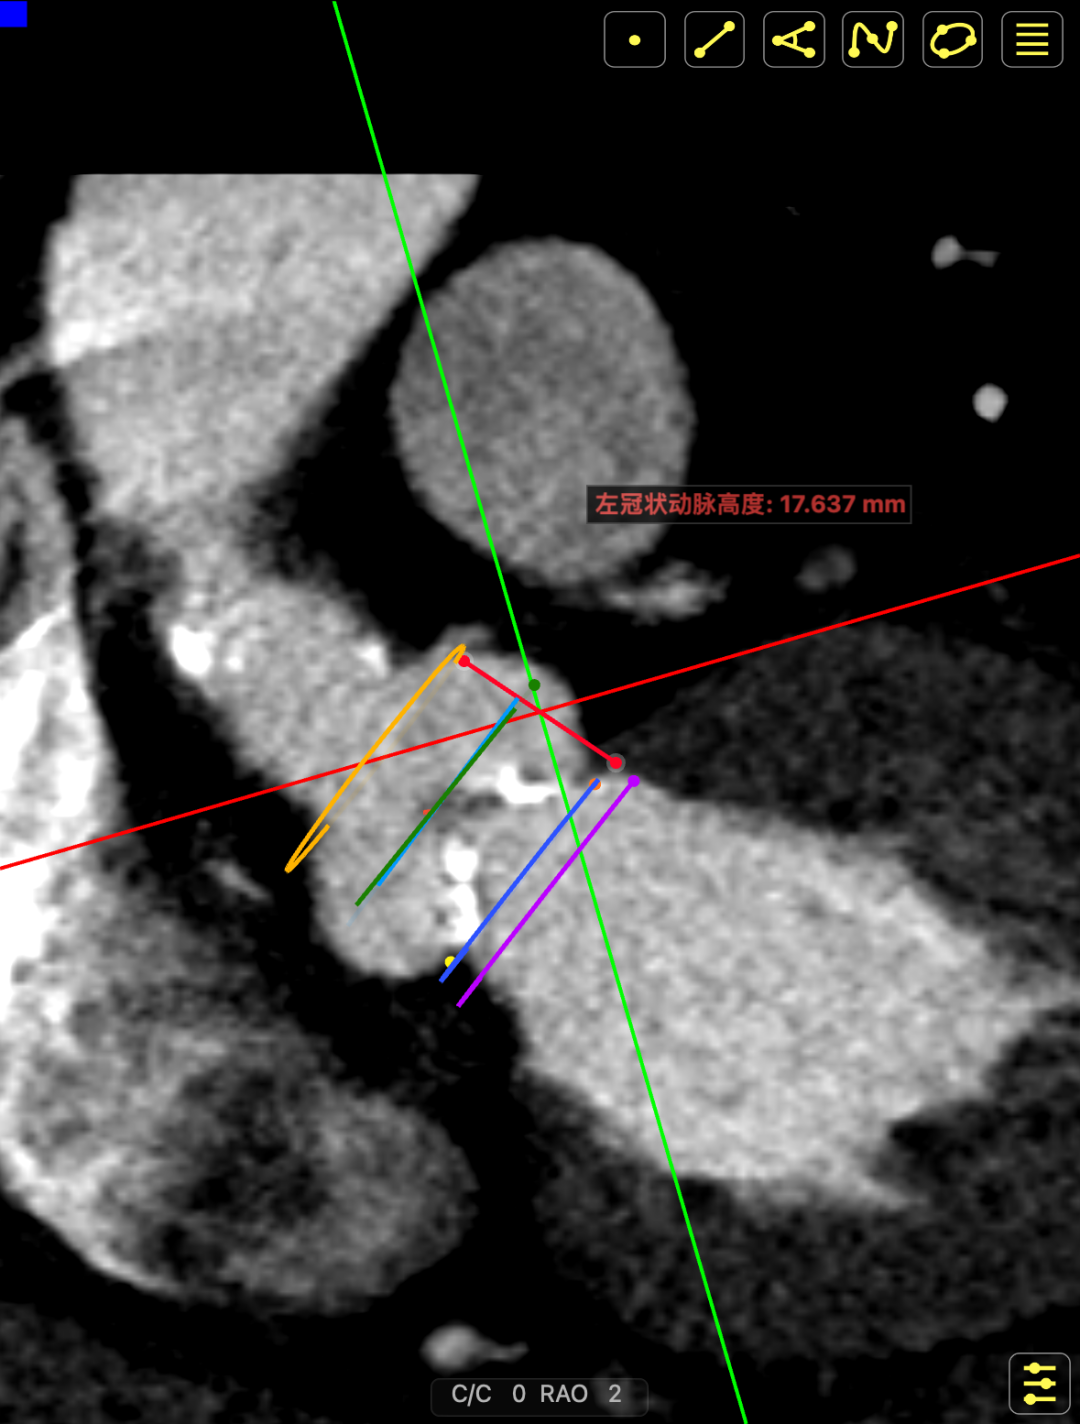

主动脉瓣多发钙化,主动脉瓣为type0型二叶瓣中重度钙化。主动脉瓣环面积折算直径约24mm。患者双侧冠脉开口高度可(左冠14.46mm,右冠18.29mm),主动脉升弓降部管壁不规则并钙化斑块影,主动脉弓并龛影。升主动脉管径36mm,降主动脉管径22mm。腹主动脉、双侧髂动脉管壁不规则并可见钙化斑块影,双侧髂总动脉及其分支髂内动脉管腔轻度狭窄。

主动脉升弓降部管不规则增厚并多发钙化,主动脉弓部左锁骨下动脉开口以远瘤样扩张,管径46*43mm。患者主动脉瓣环面积折算直径约26mm。升主动脉管径约32.5mm,降主动脉管径27.5mm;双侧冠脉开口高度可(左冠17.63mm,右冠12.18mm)。头臂血管右侧无名动脉、左侧颈总动脉、左侧锁骨下动脉管壁不规则增厚;头臂干起始部管壁钙化,管腔轻微狭窄。腹主动脉、双侧髂总动脉及其分髂内、髂外动脉管壁不规则增厚并钙化。